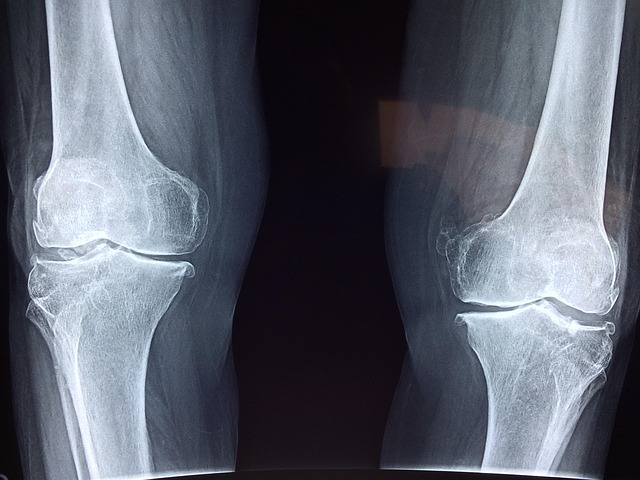

10. 뻣뻣함 및 뚝뚝 소리

관절이 뻣뻣해지고 움직일 때 뚝뚝 소리가 난다면, 이는 관절 마찰이나 연골 손상의 신호일 수 있습니다. 이러한 증상은 초기에는 무시되기 쉽지만, 점차 심각한 문제로 이어질 수 있습니다.